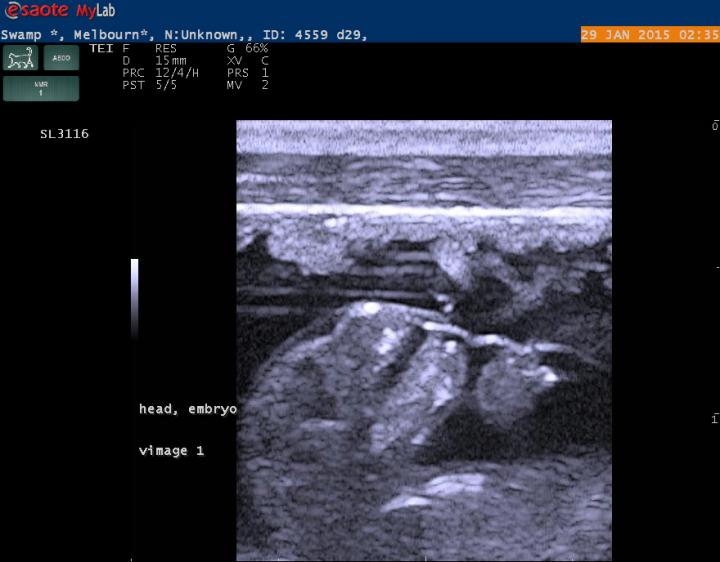

Researchers report evidence suggesting an unusual mode of reproduction in swamp wallabies. In kangaroos and wallabies, young are born immature and complete development during an extended period of lactation. Females, which possess two uteri that are alternately used for conception, normally ovulate and mate after giving birth. Suckling of the newborn in the pouch triggers signals that arrest the development of the new embryo until the newborn leaves the pouch. Brandon Menzies and colleagues report an extraordinary form of reproduction in the swamp wallaby (Wallabia bicolor), which ovulates, mates, and conceives anew while still actively pregnant--a similar phenomenon was previously reported in the European brown hare. Mature female swamp wallabies were sourced from the wild in Victoria, Australia, and experiments on 10 individuals, some of which were scanned using high-resolution ultrasound through pregnancy, revealed that swamp wallabies ovulate and mate 1-2 days before giving birth and conceive a new embryo during active pregnancy. The finding indicates that gestation length in swamp wallabies exceeds the length of the oestrous cycle. Because they become pregnant before giving birth, swamp wallabies, the findings suggest, may be continuously pregnant throughout their reproductive lives, according to the authors.